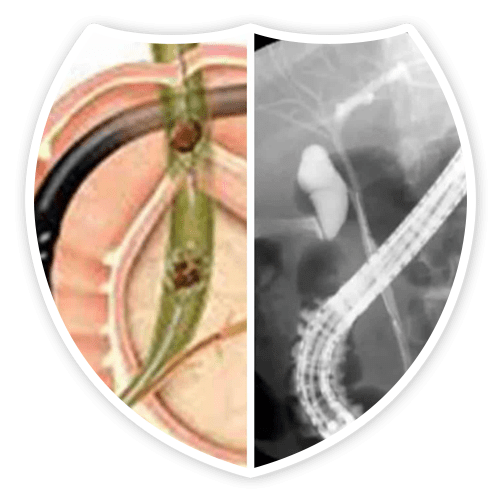

مناظير القنوات المرارية عن طريق منظار الامعاء الدقيقة DBE ERCP

عن طريق منظار الامعاء لعلاج

انسداد القنوات المرارية فى مرضى تحويل مسار للامعاء الدقيقه او تحويل مسار للقنوات المرايه سواء بسبب عمليات تحويل المسار للسمنه او أورام المعده والبنكرياس والاثنى عشر او مضاعفات عملية استئصال المرارة

مناظير القنوات المرارية ERCP